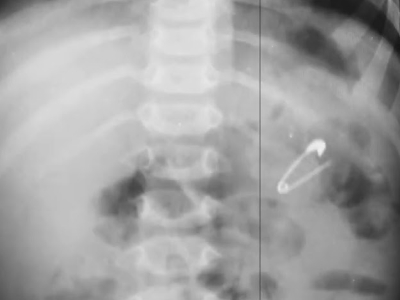

Механическое повреждение кишечника — одна из самых частых причин появления крови. Обычно это происходит после проглатывания острых костей, жёстких частей игрушек или других инородных предметов. Небольшие царапины дают алые прожилки, более глубокие — почти черный стул. При повреждении брюшной полости присоединяются боль, рвота с кровью и признаки болевого шока — ситуация требует немедленной помощи.

Травма, острые кости, инородное тело

Удаление инородного тела (эндоскопически или хирургически); обезболивание; инфузии; гастропротекторы

Убрать источник травмы; остановить кровотечение; предупредить перитонит

• Контроль игрушек и мелких предметов.

Инородные тела — одна из частых хирургических причин кровавого стула.